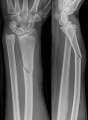

Mezi poruchy a úrazy kostry náleží např. osteoporóza (ubývání minerálů v kostech), skolióza (vybočené páteře) či zlomeniny. Ty mohou být otevřené (kost rozřízne kůži, mohou zahrnovat krvácení a obvykle jsou důvodem k volání zdravotnické záchranné služby) či uzavřené. Se zlomeninami je vhodné co nejméně manipulovat, zvláště je-li ošetření nablízku.